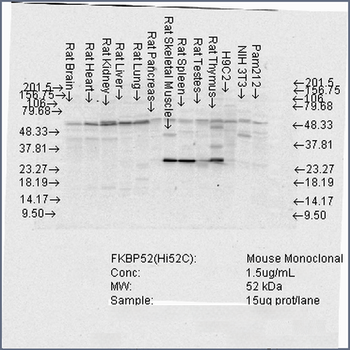

100 μgFKBP52 Antibody: Biotin [orb147211]

ELISA, ICC, IF, IHC, WB

Canine, Hamster, Human, Mouse, Rat

Mouse

Monoclonal

Biotin

100 μg